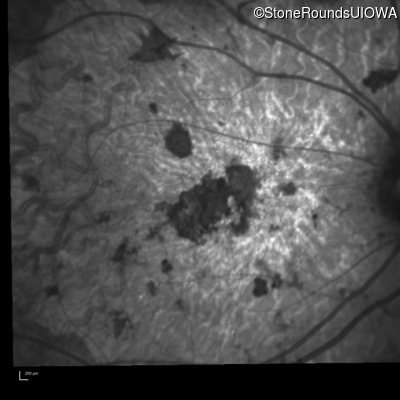

Infrared Fundus Photograph - Right - 20/150 sc

Exemplar